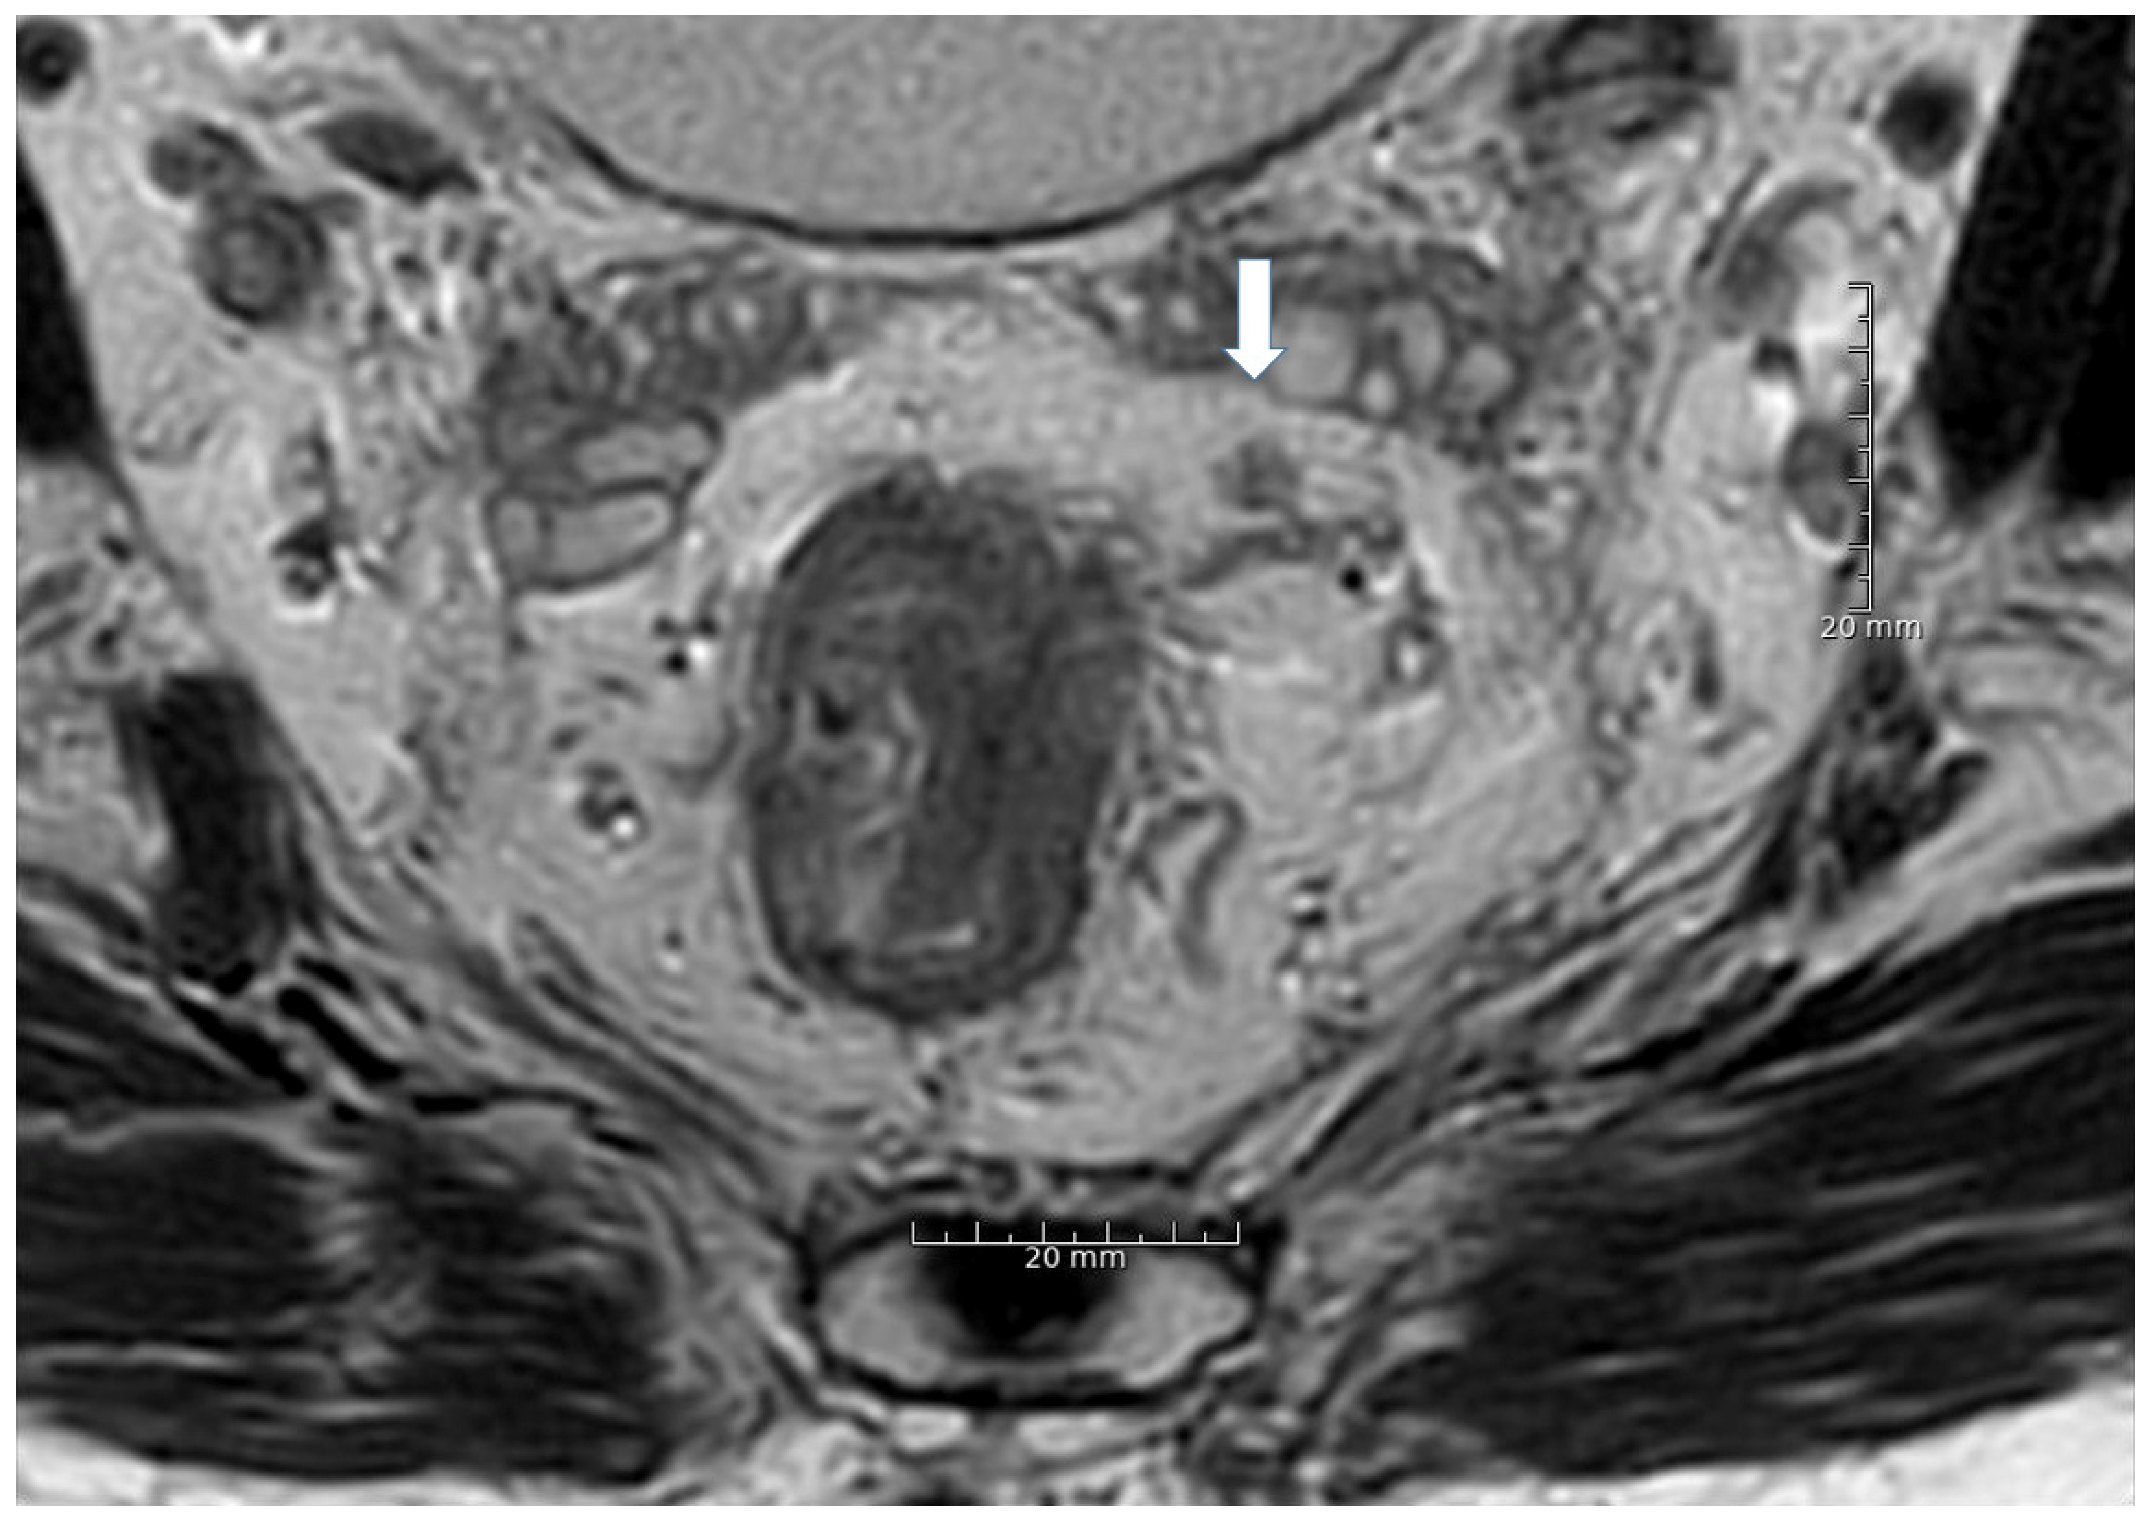

2.3. Lymph Node Assessment